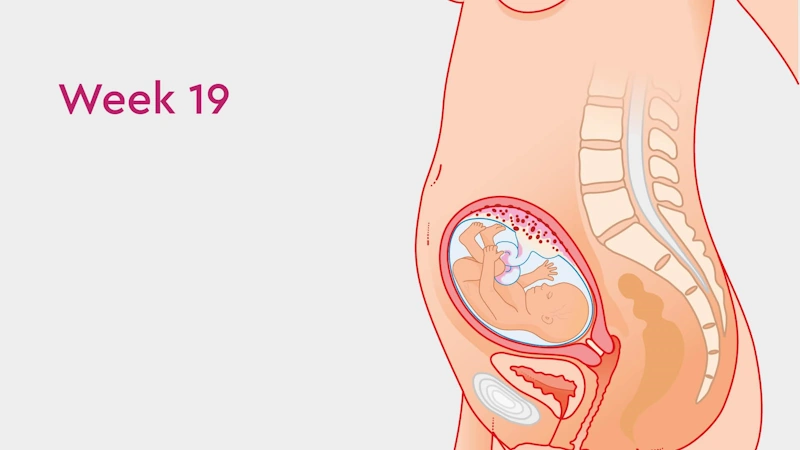

در هفته نوزدهم بارداری، بدن شما و جنین ۱۹ هفتهای وارد مرحلهای هیجانانگیز میشوند. پوست حساس جنین با لایهای سفید و چرب به نام ورنیکس کازئوزا پوشیده میشود؛ مادهای طبیعی که از پوست او در برابر مایع آمنیوتیک محافظت میکند و مانع چروک شدنش تا زمان تولد میشود.

در همین زمان، ریههای جنین در هفته ۱۹ بارداری به سرعت رشد میکنند و شاخههای هوایی اصلی (برونشیولها) شکل میگیرند. شاید در این هفته برای نخستین بار حرکتهای ظریف و آرام جنین را در شکم خود احساس کنید. اگر هنوز این حس را تجربه نکردهاید، نگران نباشید — خیلی زود این لحظه زیبا فرا میرسد.

در هفته نوزدهم بارداری، جنین شما به سرعت در حال رشد است و وزن جنین ۱۹ هفتهای حدود ۱۹۰ تا ۲۰۰ گرم و قد او نزدیک به ۲۰ سانتیمتر است؛ تقریباً به اندازه یک موز بزرگ 🍌.

اکنون چشمها و گوشهای جنین در جای نهایی خود قرار گرفتهاند و اگر سونوگرافی انجام دهید، ممکن است بتوانید چهرهاش را تشخیص دهید — حتی بینی یا چانهاش شبیه شما یا پدرش باشد!

بدن جنین در هفته ۱۹ بارداری پر از تحرک است. او حالا میتواند دستها و پاهایش را بکشد، مشت کند یا حتی انگشت شست خود را بمکد.